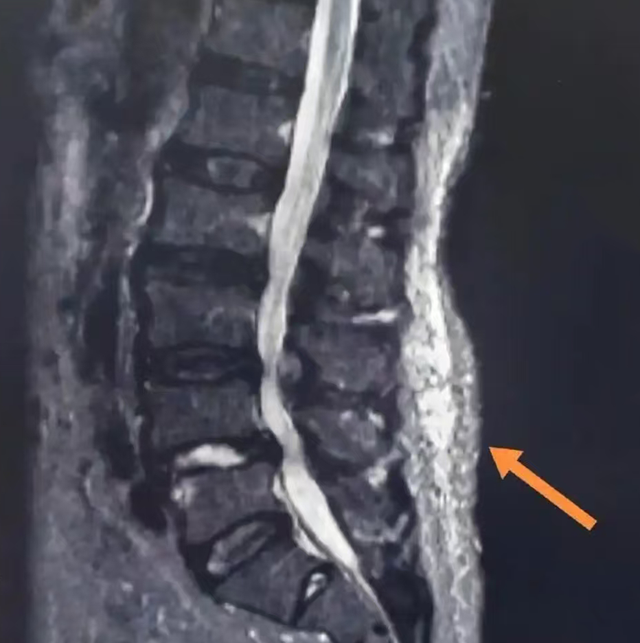

其实,你可能遇上了“肌筋膜炎”——这种在肌肉骨骼疾病中占比高达30%~85%的常见问题,正是颈肩腰背隐痛、酸胀的“幕后黑手”。